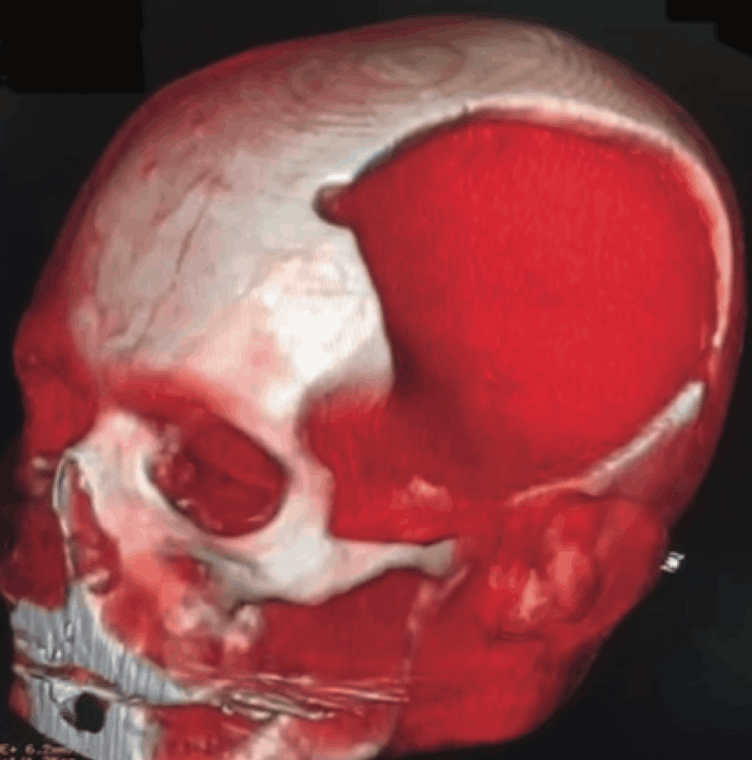

Cranioplasty For Treatment of Syndrome of The Trephined: Case Report And Literature Review.

Por Dr. Chrystiano Fonseca Cardoso.

Syndrome of the Trephined (ST) is a neurological complication observed after decompressive craniectomies, characterized by progressive neurological deterioration associated with the removal of a significant portion of the skull. ST is commonly seen in patients with severe traumatic brain injury, stroke, or other conditions that cause intracranial hypertension. Although rare, its clinical relevance is significant due to its impact on patient recovery.

The incidence of ST varies depending on the clinical context and region, with risk factors such as hemorrhagic injuries and brain displacement. In Brazil, the prevalence of the syndrome is underreported, partly due to the lack of large-scale studies, but its incidence has been increasing as decompressive craniectomies are more commonly performed in patients with severe intracranial hypertension.